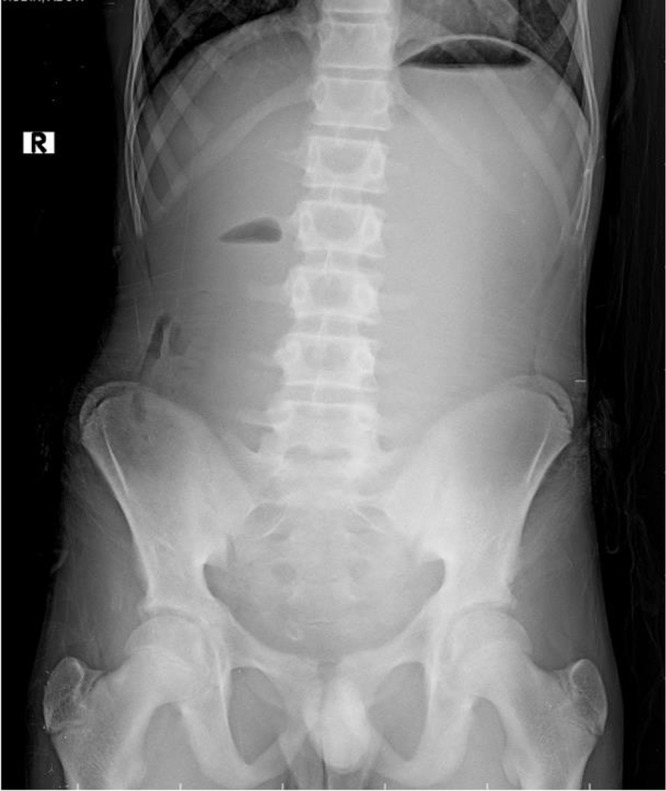

Superior mesenteric artery (SMA) syndrome, also known as Wilkie syndrome, is an uncommon condition marked by the compression of the third segment of the duodenum between the SMA and the aorta, often occurring after rapid weight loss, particularly in young, slim individuals. Symptoms consist of epigastric pain, bloating, and vomiting. Nutcracker syndrome (NCS) is characterized by the compression of the left renal vein (LRV) between the superior mesenteric artery and the aorta. This condition results in venous varices and elevated pressure within the LRV, which may manifest as hematuria, proteinuria, pelvic congestion, and flank pain. Although each of these syndromes is infrequent, their simultaneous incidence is remarkably occasional. This case report examines a young male patient diagnosed with both SMA syndrome and NCS, emphasizing the importance of considering these conditions in the differential diagnosis of abdominal and renal symptoms.